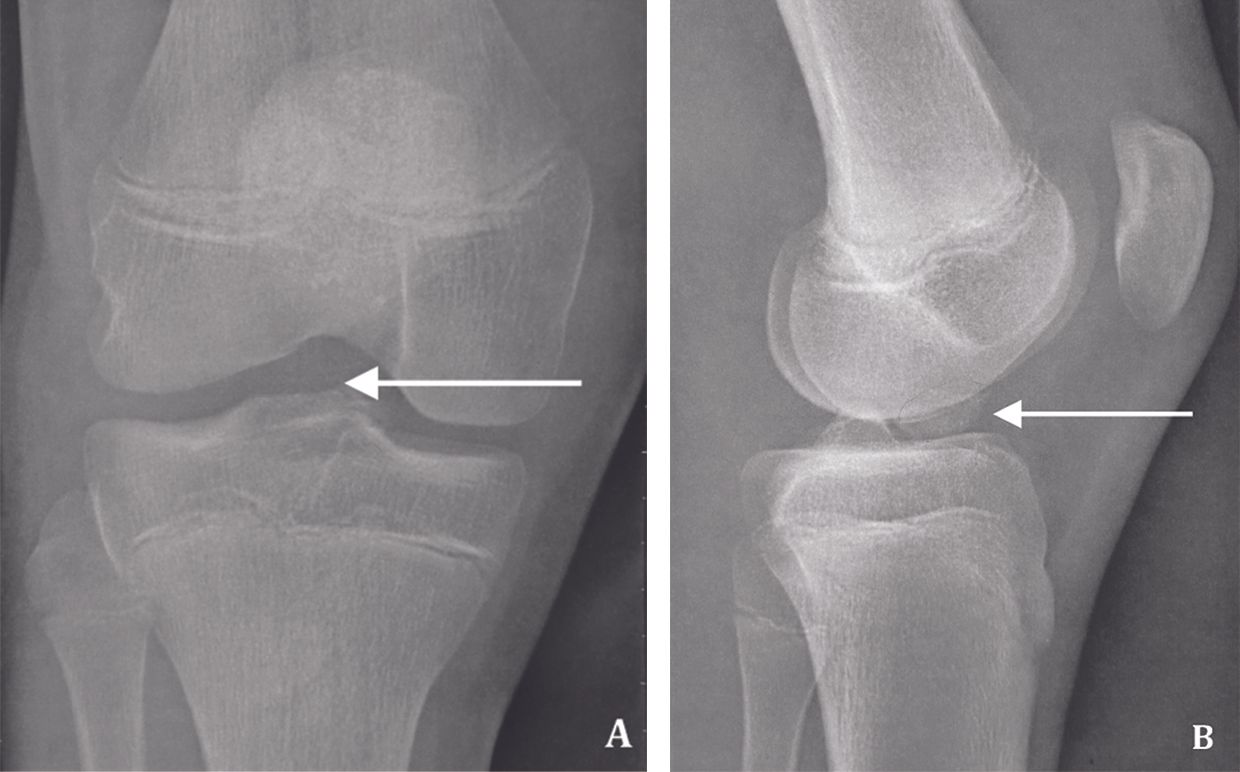

Technique Traitement d’une fracture des épines tibiales par suture sur une ancre résorbable sous arthroscopie , Martin Cholley-Roulleau Interne des hôpitaux, Nancy, France , Olivier Gosselin Clinique Claude Bernard, Metz, France N°279 - Décembre 2018 ● 13 min de lecture